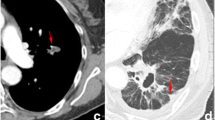

The aim of this study was to apply density correction method to the quantitative image analysis of non-small cell lung cancer (NSCLC) computed tomography (CT) images, determining its influence on overall survival (OS) prediction of surgically treated patients. Clinicopathological (CP) data and preoperative CT scans, pre- and post-contrast medium (CM) administration, of 57 surgically treated NSCLC patients, were retrospectively collected. After CT volumetric density measurement of primary gross tumour volume (GTV), aorta and tracheal air, density correction was conducted on GTV (reference values: aortic blood and tracheal air). For each resulting data set (combining CM administration and normalization), first-order statistical and textural features were extracted. CP and imaging data were correlated with patients 1-, 3- and 5-year OS, alone and combined (uni-/multivariate logistic regression and Akaike information criterion). Predictive performance was evaluated using the ROC curves and AUC values and compared among non-normalized/normalized data sets (DeLong test). The best predictive values were obtained when combining CP and imaging parameters (AUC values: 1 year 0.72; 3 years 0.82; 5 years 0.78). After normalization resulted an improvement in predicting 1-year OS for some of the grey level size zonebased features (large zone low grey level emphasis) and for the combined CP-imaging model, a worse performance for grey level co-occurrence matrix (cluster prominence and shade) and first-order statistical (range) parameters for 1- and 5-year OS, respectively. The negative performance of cluster prominence in predicting 1-year OS was the only statistically significant result (p value 0.05). Density corrections of volumetric CT data showed an opposite influence on the performance of imaging quantitative features in predicting OS of surgically treated NSCLC patients, even if no statistically significant for almost all predictors.